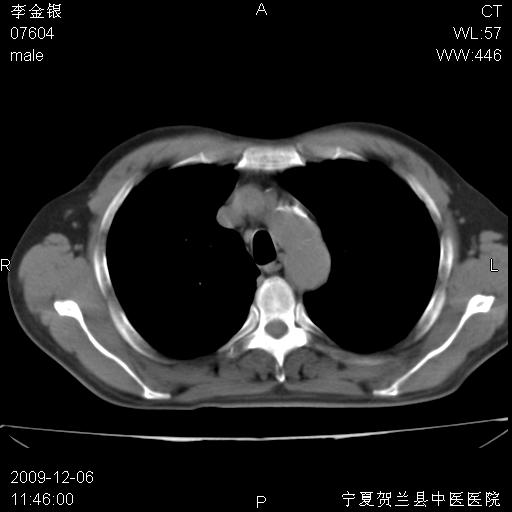

考虑右肺中央型占位性病变并阻塞性肺炎.(右肺上叶支气管变窄),建议支纤镜检查.

考虑右肺中心型肺癌伴阻塞性肺炎及右肺门淋巴结转移,建议纤维支气管镜进一步检查。

支气管壁明显增厚 管腔狭窄,腔静脉后多个淋巴肿大,结合年龄病史考虑右肺上叶中央型肺癌并阻塞性肺炎

右肺上叶后段支气管阻塞,右上肺门占位,相应肺段阻塞性肺炎,右肺门有淋巴结肿大。诊断右肺上叶中心型肺癌,阻塞性肺肺炎、右肺门淋巴结转移。